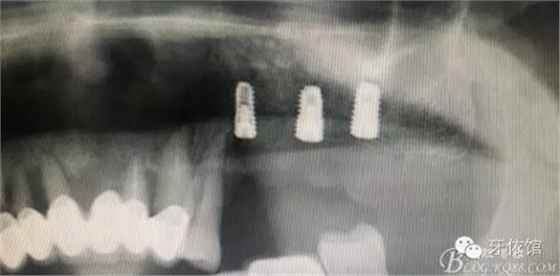

患者男性,62歲,X光片顯示竇底有二維20x15mm囊腫,竇膜內(nèi)無(wú)內(nèi)容物

計(jì)劃:1.外開(kāi)窗2.摘除囊腫3.植骨期植入植體

植骨量1.5g